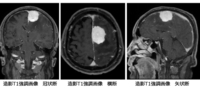

【CT,MRI画像あり】髄膜腫の手術適応の基準は?症状や治療、再発まとめ

髄膜腫 meningiomaいろいろな髄膜腫を見たい方はここをクリックここから下は難しいです髄膜腫の病理はここをクリック